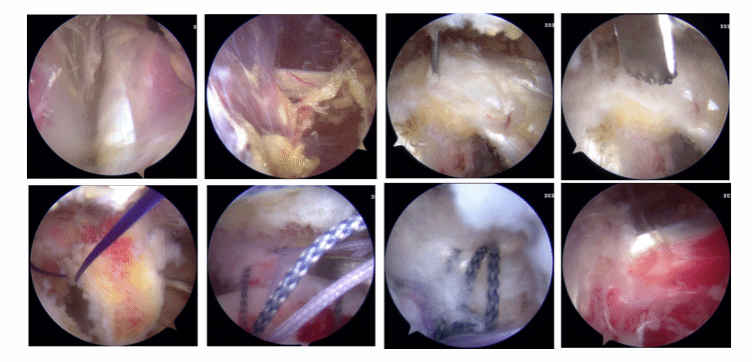

全镜下Bristow手术

在国际上首创关节镜下改良“嵌入式”喙突移位(Bristow)手术,并将其命名为CUIstow手术(Chinese Unique Inlay Bristow)

全镜下Latarjet手术

近年来,开始开展全镜下喙突移位Bristow,Latarjet手术治疗肩关节复发性脱位。目前已经可以在2个小时内完成高难度的全镜下Bristow,Latarjet手术。崔国庆教授受到中国古建筑学中“榫卯”结构的启发,将之引入经典的Bristow手术中,在国际上首创关节镜下改良“嵌入式”喙突移位(Bristow)手术,并将其命名为CUIstow手术(Chinese Unique Inlay Bristow),通过增加骨接触愈合面积,显著增加了移植喙突骨块的稳定性并且极大提高了术后的骨愈合率。截至目前为止,该手术技术在课题组所在单位已经成功实施400余例,3年中期随访结果显示,术后骨愈合率达到了96.4%,并发症的发生率仅为3.6%,术后重返运动比率达到了98%,取得了非常良好的临床效果以及患者满意度。相关成果发表在国际运动医学领域权威期刊American Journal of Sports Medicine,AJSM和国际骨与关节领域权威期刊Journal of Bone & Joint Surgery,JBJS。